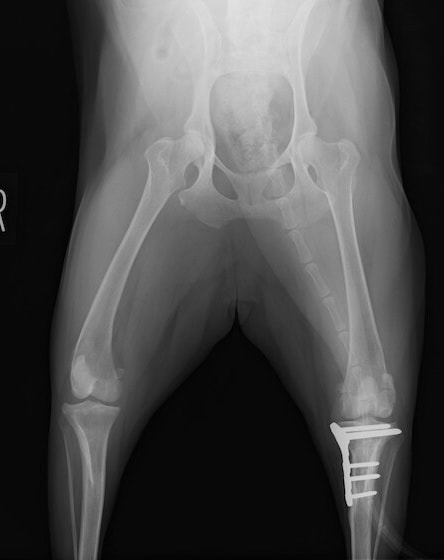

術前正面像

術後左後肢正面像

術前のTPAは左後肢33.1°右後肢26.8°でしたがTPLO実施により左後肢5.5°右後肢12°に矯正されました。